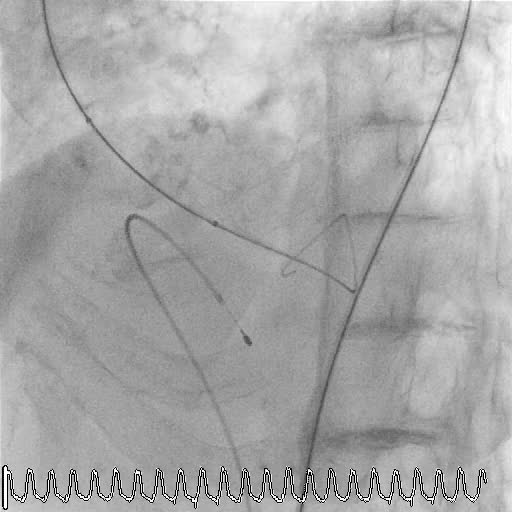

MITRALCLIP – La fusion imaging

Categoria: Relazioni storiche Parole chiave: ecotee ecotee3d interventistica mitraclip

Autore: Eustachio Agricola

Anno: 2020